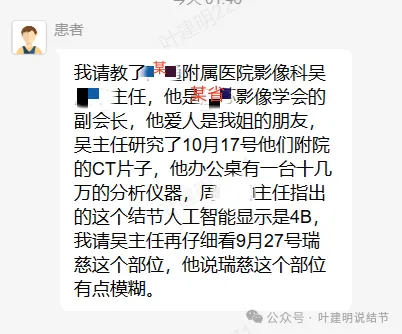

当地附属医院影像科吴姓主任,是该省影像学会的副会长有台十几万的分析仪器。结友没说吴主任具体意见。

上海中山医院王群教授意见是考虑炎症可能性大,建议3个月复查。